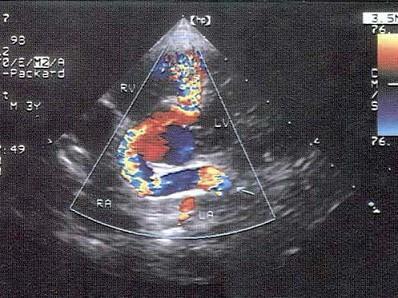

该病例最可能的诊断?(?)A.冠状动脉瘤B.右冠状动脉瘘C.川崎病D.冠状动脉起源异常E.室间隔缺损

选项 A.冠状动脉瘤 B.右冠状动脉瘘 C.川崎病 D.冠状动脉起源异常 E.室间隔缺损

答案 B